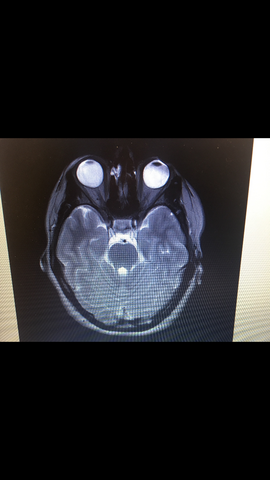

MRT-Bilder schenken uns Einblicke ins menschliche Gehirn. Schonende Methode: Die MRT-Untersuchung im "Kernspin" kommt ohne. Eine MRT (Kopf- und Halsbereich) wird vor allem in der Neurologie durchgeführt, um krankhafte Veränderungen oder Verletzungen im Schädelbereich festzustellen.